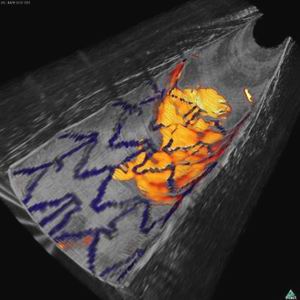

结合光学成像和近红外荧光图像显示兔子动脉内表面,蓝色为植入的支架,红黄色为纤维蛋白沉积

为了检验这款探针,Tearney的团队先是喂食了产生动脉积垢的兔子,并用荧光对危险信号分子进行标记。探针的探测器带有荧光进入了动脉,在动脉壁上显示亮区标记他们发现的目标。

这个小组能够检测到一种引发血块形成的纤维蛋白,和组织蛋白酶B的形成,在最危险的斑块中有发现这样的酶。

检测纤维蛋白对于那些患有动脉阻塞并通过支架手术进行疏通的患者非常重要,因为手术后血管很快会再次阻塞,而再次阻塞的第一迹象就是支架上的纤维蛋白沉积。

目前的探针无法区分正常的纤维蛋白沉淀,比如支架上的那些细胞。但荧光检测可以,所以医生可以在血栓形成前给患者开溶解血块的药物。